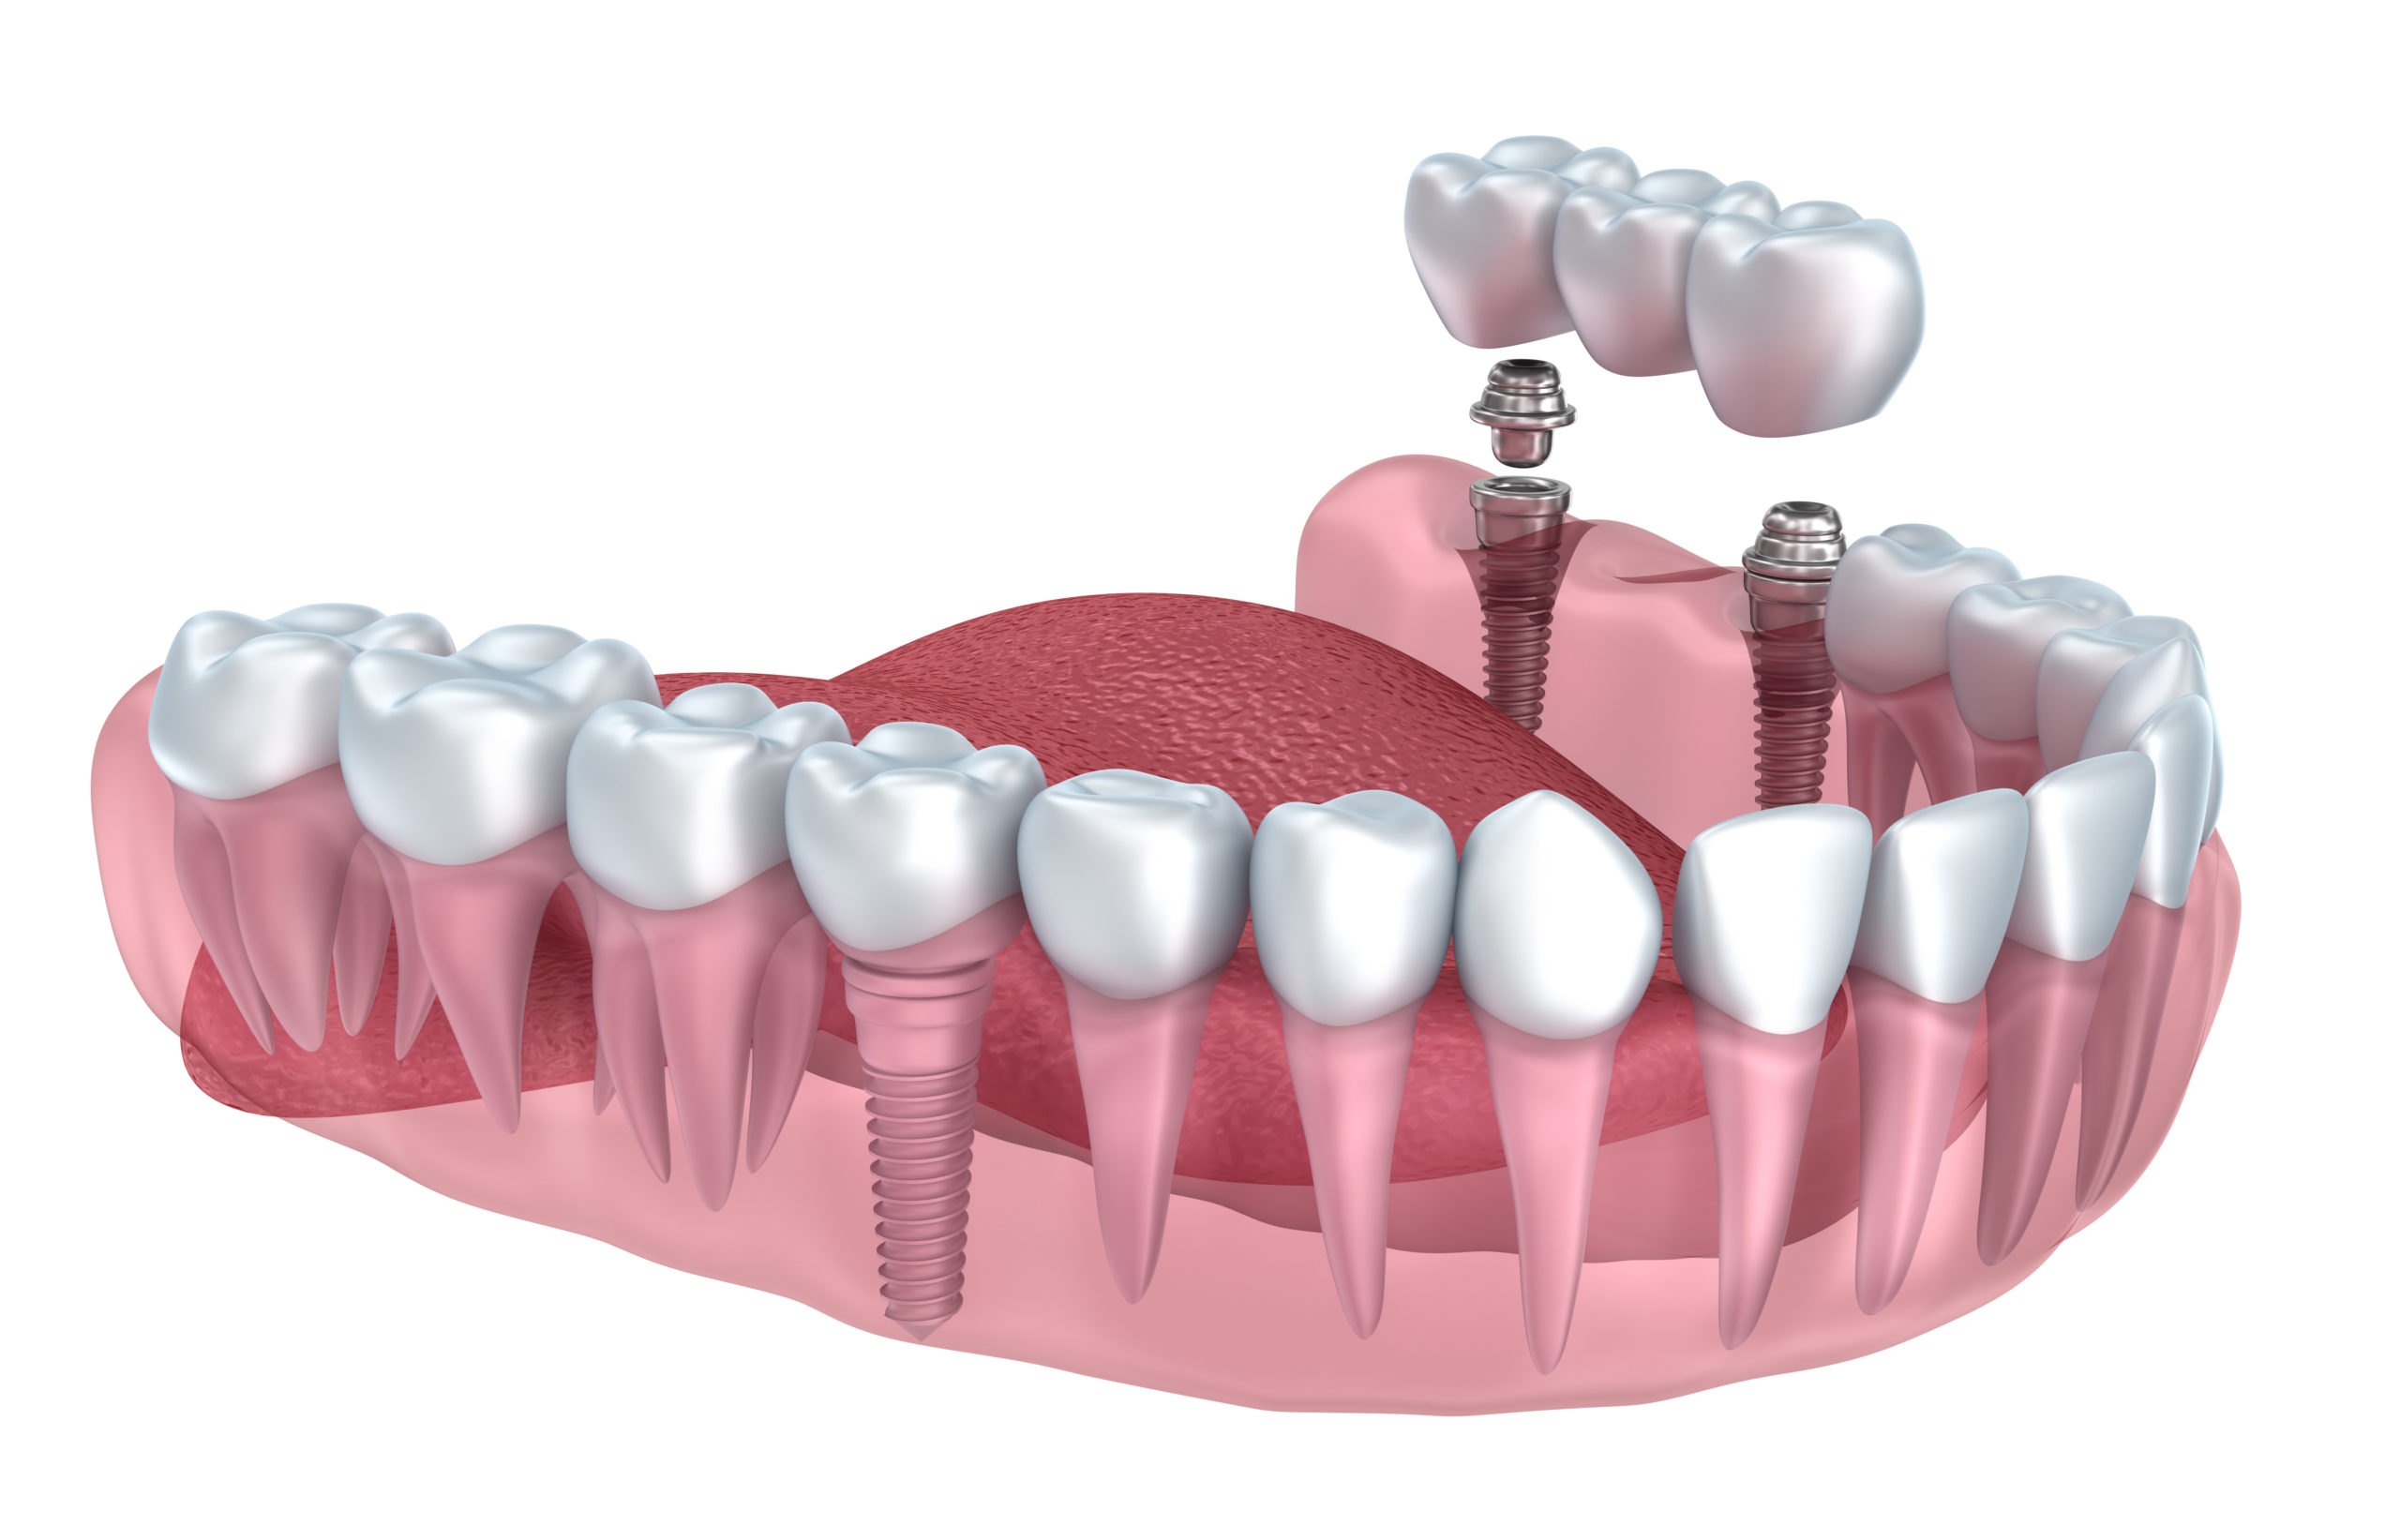

Oral implantology is the branch of dentistry that specializes in replacing missing teeth using an artificial root, secured in the bone to hold single teeth, groups of teeth or to act as a support for a complete prosthesis (dentures).

Dental implants provide up to date and efficient results and have a number of advantages compared with traditional methods used in dentistry. When one or more teeth are missing, a bridge positioned on implants guarantees exceptional solutions. In the past, when a tooth was lost, the healthy, adjacent tooth/teeth had to be filed down in order to carry a bridge or a mobile prosthesis. These days we can insert an implant and on the same day position a new tooth, where necessary and feasible. In more complex cases between 4 and 8 implants per dental arch can be inserted and patients can have their new teeth within 24 hours.

Implants are available in various designs, shape and sizes that adapt to all personal and therapeutic requirements. The most used is the titanium pillar. Totally biocompatible, it does not provoke rejection, fusing comfortably with the mandibular and jaw bones. A titanium implant abutment is then screwed onto the pillar and topped with a ceramic tooth, made-to-measure by specialized dental technicians. When a new ceramic tooth is completed and positioned on the implant, it completely blends in with the adjacent natural teeth.

Multiple dental implants

After a period of stabilization of the implant and healing of the gum, varying between 3 and 6 months, the final porcelain bridge is cemented or screwed. Comfortable chewing is recuperated, and patients can smile naturally.

Fixed prostheses on implants

They are dental crowns usually made of ceramic or zirconium or composite. They are cemented or screwed onto implants.